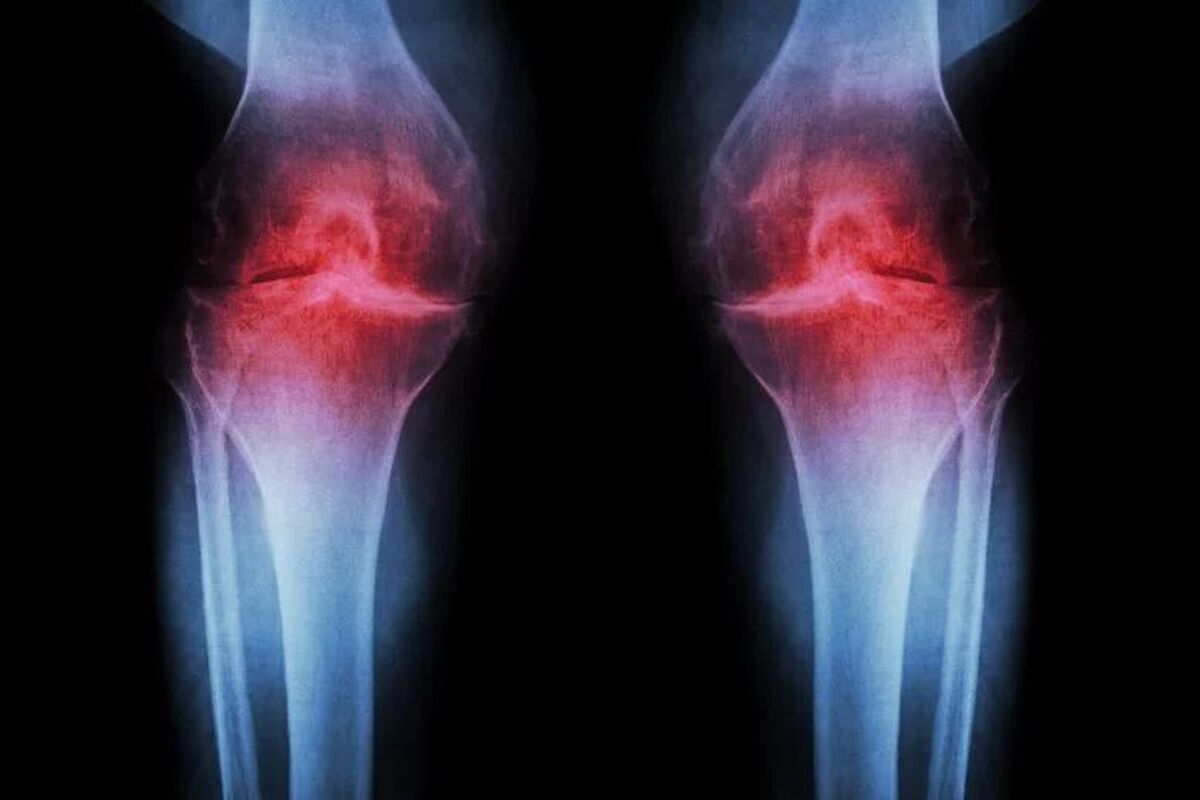

امید تازه برای درمان آرتروز؛ بازسازی غضروف با یک داروی جدید

به گزارش مگ ماه، وبگاه سایتِکدِیلی در گزارشی آورده است: موفق به توسعه یک روش درمانی انقلابی شدهاند که میتواند غضروف فرسوده زانو را بازسازی کند.

این درمان با مسدودکردن یک پروتئین پیری خاص، نه تنها غضروف را در موشهای مسن ترمیم میکند، بلکه از بروز آرتروز پس از آسیبهای جدی مانند پارگی رباط صلیبی (ACL) نیز جلوگیری میکند.